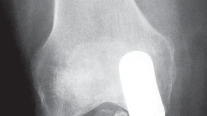

التصوير الطبي ضروري لتأكيد التشخيص وتحديد مدى تلف المفصل:

-

الأشعة السينية العادية (Plain Radiographs):

- المنظر الأمامي الخلفي (AP): يُظهر الركبة من الأمام.

- المنظر الجانبي (Lateral): يُظهر الركبة من الجانب.

- المنظر الخلفي الأمامي المثني (PA Flexed): يسمح بتقييم أفضل للجزء الخلفي من الركبة وقد يكشف عن تغيرات أكبر في الحجرة الخلفية الوحشية.

- منظر شروق الشمس (Sunrise/Patellofemoral): لتقييم المفصل الرضفي الفخذي.

- الأشعة السينية الطويلة للطرف السفلي بالكامل (Full-length standing radiographs): من الورك إلى الكاحل، وهي مفيدة جدًا، خاصة إذا تم استخدام تقنيات الملاحة الحاسوبية. تُظهر هذه الأشعة المحاذاة الكلية للطرف السفلي.